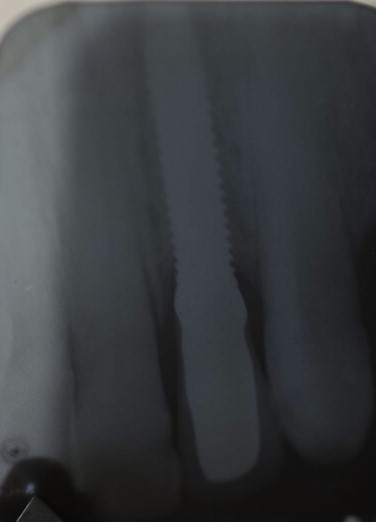

After a twenty-month follow-up (Fig. 12), complications such as loosening or fracture of the prosthetic screw and implant fracture were not observed [13]. Additionally, no bone loss was observed in the peri-implant bone area. The patient is pleased with the rehabilitation.

Fig. 12.

Radiographic image after 20-month follow up.